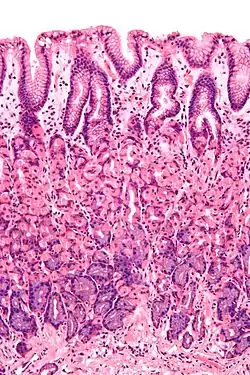

Simple columnar epithelium is a single layer of columnar epithelial cells which are tall and slender with oval-shaped nuclei located in the basal region, attached to the basement membrane. In humans, simple columnar epithelium lines most organs of the digestive tract including the stomach, and intestines. Simple columnar epithelium also lines the uterus.

Simple columnar epithelium is further divided into two categories: ciliated and non-ciliated (glandular). The ciliated part of the simple columnar epithelium has tiny hairs which help move mucus and other substances up the respiratory tract.

The shape of the simple columnar epithelium cells are tall and narrow giving a column like appearance. the apical surfaces of the tissue face the lumen of organs while the basal side faces the basement membrane.[1] The nuclei are located closer along the basal side of the cell.[1]

Absorptive columnar epithelium is characterized as having a striated border on its apical side, this border is made up of non-motile microvilli allowing for increase surface area for absorption.[1] These are known as non-ciliated columnar epithelium. Non-ciliated simple columnar epithelium is made up of glandular goblet cells which secrete mucin to form mucus.[1] The rest of the cell is made up of cytoplasm with membrane bound secretory granules which secrete the mucin, and are found towards the apical surface of the cell.[1]

Vertical section of a villus from the dog's small intestine. X 80. (Simple columnar epithelium labelled at right, third from the top.)

Transverse section of a villus, from the human intestine. X 350.

a. Basement membrane, here somewhat shrunken away from the epithelium.

b. Lacteal.

c. Columnar epithelium.

d. Its striated border.

e. Goblet cells.

f. Leucocytes in epithelium.

f’. Leucocytes below epithelium.

g. Blood vessels.

h. Muscle cells cut across.